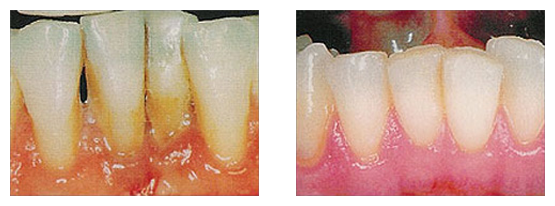

Bei Menschen über 40 fallen dem Zahnfleischschwund mehr Zähne zum Opfer als durch Karies. Durch Speisereste und Beläge entzündet sich das Gewebe und schwillt an. Wird die Erkrankung frühzeitig erkannt, können Spätfolgen wie Zahnverlust verhindert werden.

Für die Parodontitisbehandlung gibt es mittlerweile sehr moderne und schonende Verfahren.

Parodontitis behandeln wir mit der nahezu schmerzfreien Vector-Therapie. Dabei werden die empfindlichen Zahnwurzeln mit Ultraschallinstrumenten gereinigt – es wird nicht gekratzt oder geschliffen. Ein zusätzlich verwendetes Poliermittel sorgt ähnlich einer Zahncreme dafür, dass der für die Parodontitis verantwortliche Biofilm sicher beseitigt wird.

Entzündete Zahntaschen werden mit Hilfe einer Spülflüssigkeit gereinigt. Nach einer angemessenen Zeit wird kontrolliert, ob die Entzündung abgeheilt ist. Bei Bedarf werden die betroffenen Stellen nachbehandelt.